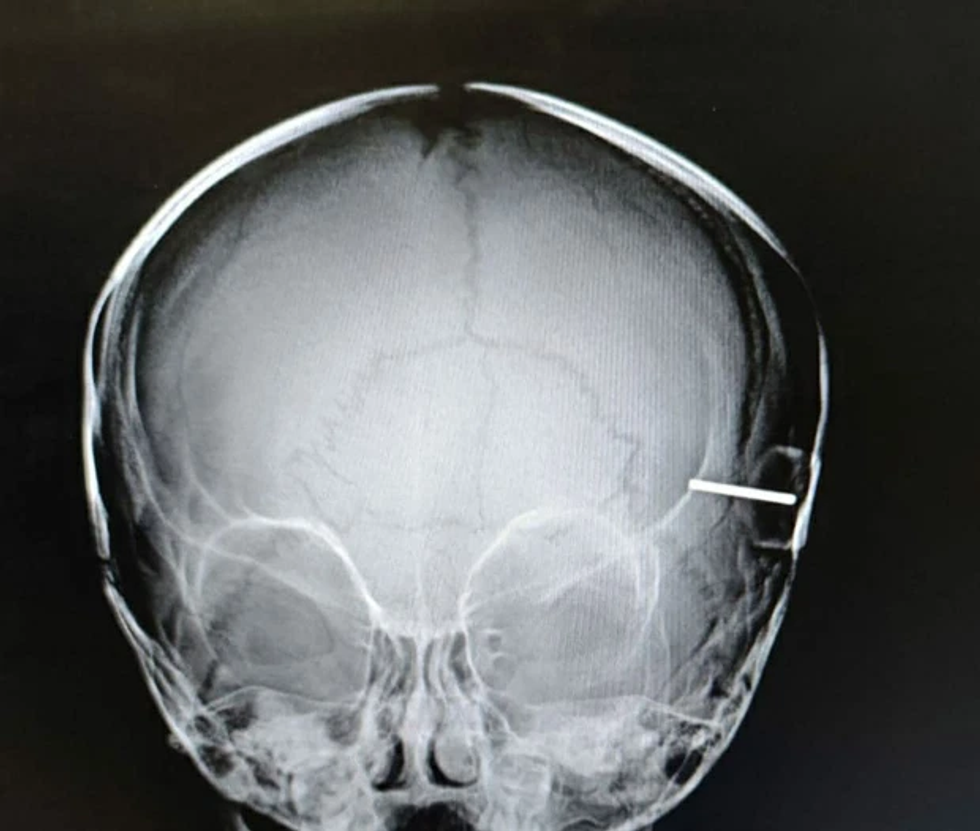

Doktorët kanë arritur të shpëtojnë një bebe vajzë 10-muajshe pas një aksidenti horror ku boshti i rrotës së lodrës së saj iu ngul në kafkë, disa milimetra larg trurit.

Në grafitë me rreze X shihej sesi metali kishte depërtuar në kafkën e vogëlushes dhe doktorët fillimisht besonin se kishte shpuar trurin e saj.

Doktorët e spitalit të fëmijëve Speransky, zbuluan më tej se sipërfaqja e trurit të saj nuk ishte dëmtuar dhe vijuan të heqin objektin duke përdorur një “instrument special “.

Kirurgu Ruslan Molotov tha: “Ne duhet të siguroheshim që asnjë pjesë e objektit të mos mbetej në brendësi dhe në zonën e dëmtuar”. Ai shtoi se fëmija nuk do të ketë dëme të përhershme nga incidenti.